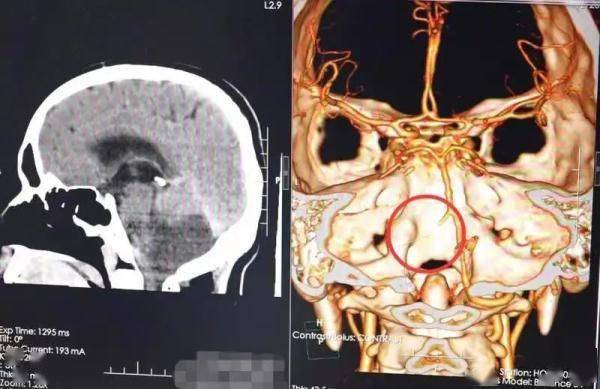

该院接诊的神经外九科主任穆林森仔细观察患者的体征 , 结合外院的影像检查资料 , 认为小脑梗死诊断明确 。 完善相关检查后 , 穆林森发现患者有小脑扁桃体下疝 。

文章图片

检查提示患者脑梗死 。 通讯员供图

为避免脑疝进一步加重导致呼吸心跳骤停等严重后果 , 10月30日 , 穆林森团队为患者急诊实施了后颅窝去骨瓣减压术和右侧脑室外引流术 , 顺利切除了部分梗死的小脑组织 。